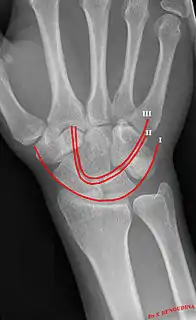

Gilula carpal arcs.

Gilula's lines are three arcs drawn on an AP radiograph of the wrist used to assess the alignment of the carpal bones.[1]

There should be no step-off in the contour of the lines when drawn on a normal wrist.

First arc running along the proximal convexity of the scaphoid, lunate and triquetrum

Second arc running along the distal concavities of the scaphoid, lunate and triquetrum

Third arc running along the proximal curvatures of the capitate and hamate